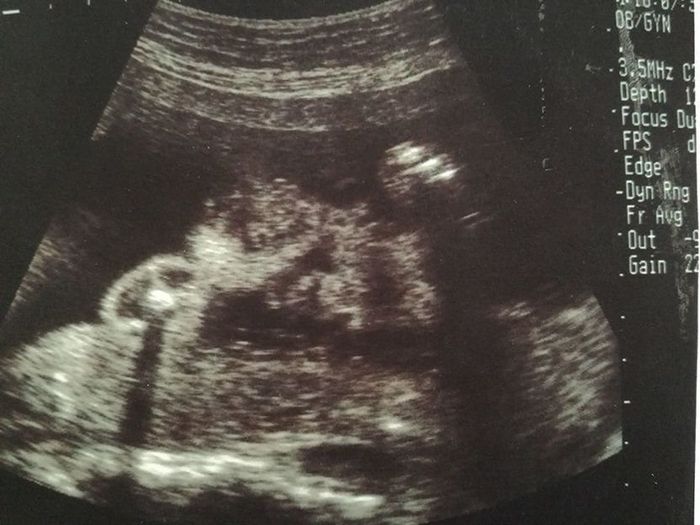

妊娠34週目のエコー写真

推定体重は、平均よりやや大きめの2328g。すくすく育っているのは嬉しい限り。相変わらず、赤ちゃんは性別が分からないように隠しているので、名前も男の子と女の子の2バージョンをいくつか考えて、各候補を絞り始めていました。こだわり出すとキリがないのですが、名前はパパとママが最初に贈ることができるプレゼントだからと、一生懸命に考えていました。